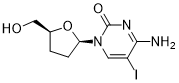

馬鞍山致研生物醫(yī)藥科技有限公司成立于馬鞍山市鄭浦港新區(qū)現(xiàn)代產(chǎn)業(yè)園。公司專(zhuān)注于生物小分子、醫(yī)藥中間體相關(guān)產(chǎn)品的研發(fā)和生產(chǎn),產(chǎn)品主要包括DNA亞磷酰胺單體、RNA亞磷酰胺單體、特殊單體以及按照客戶(hù)要求定制的RNA和DNA,并且公司提供定制合成等方面的研究服...

馬鞍山致研生物醫(yī)藥科技有限公司成立于馬鞍山市鄭浦港新區(qū)現(xiàn)代產(chǎn)業(yè)園。公司專(zhuān)注于生物小分子、醫(yī)藥中間體相關(guān)產(chǎn)品的研發(fā)和生產(chǎn),產(chǎn)品主要包括DNA亞磷酰胺單體、RNA亞磷酰胺單體、特殊單體以及按照客戶(hù)要求定制的RNA和DNA,并且公司提供定制合成等方面的研究服...